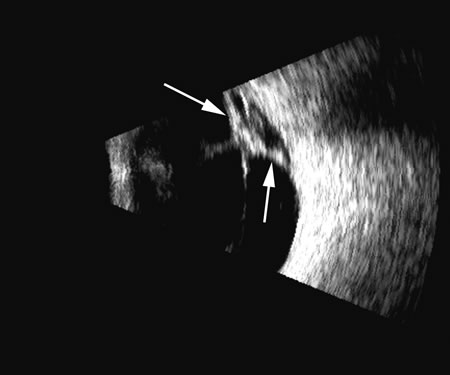

There are several tumors that invade the vitreous or the vitreous space. In children, retinoblastoma can seed the vitreous; in adults, reticulum cell sarcoma can cause vitreous clouding but is nondiscernible from other forms of debris. A very high percentage of retinoblastomas contain calcium, which is very reflective (Fig. 20). Malignant melanoma, hemangioma, metastatic carcinoma, and subretinal hemorrhage can all present with elevated convex lesions that protrude or extend into the vitreous space and are the four most commonly seen posterior segment tumors. Anteriorly, medulloepithelioma (diktyoma) and melanocytoma or ciliary body cysts can also protrude into the vitreous. The differentiation of these tumors has been well described with conventional combined B- and A-scan ultrasound techniques2 and standardized A-scan echography,28 as well as more modern spectral analysis techniques. These all provide excellent means of differentiating solid from cystic lesions, but differentiation between diktyoma (medulloepithelioma), melanocytoma, and melanoma is not possible with A-scan or B-scan.

Fig. 20. An eye filled with a retinoblastoma, which has considerable calcium deposits that produce a very reflective, high-amplitude echogenic structure (arrows).